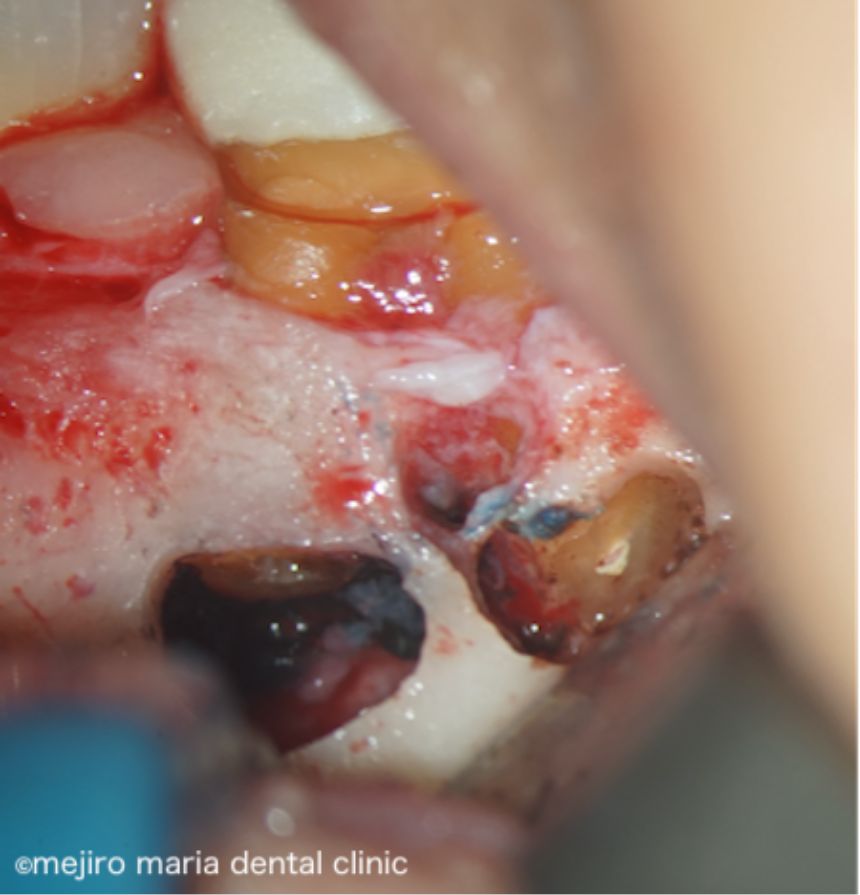

当院にて根管治療を開始するも根管治療の反応は乏しく、術前に確認できていた症状の改善は認められませんでした。その為、この患者様には歯根端切除術を追加で行い、マネージメントをさせていただくこととなりました。

歯根端切除術時に根尖を3mmほど切断したところ、根尖を取り囲むほどの歯石が確認され、この歯石の感染が根尖性歯周炎の治癒を妨げていた可能性がありました(写真)。